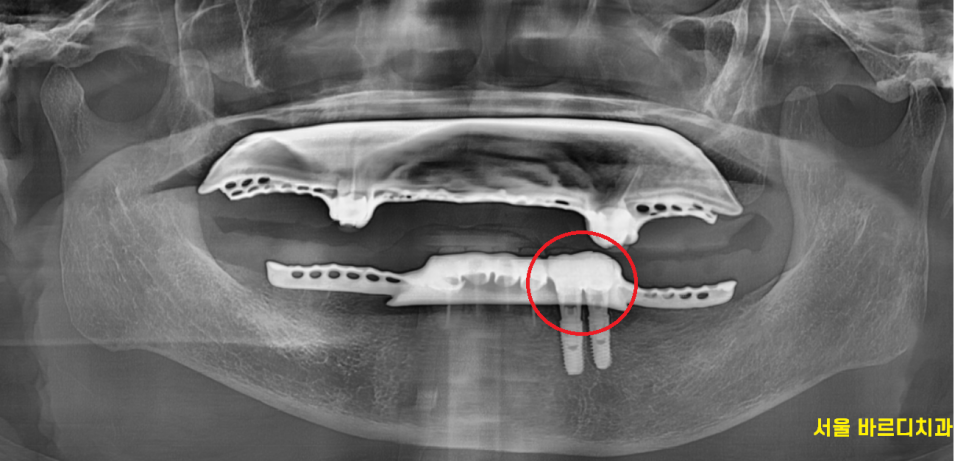

임플란트로 교체 하고나면

단순히 수술로 끝나서는 안됩니다.

일반적으로는 임플란트는 머리 완성 후

교합을 맞춰드리고 치료는 종결이지만

틀니 사용중 치아 부러짐으로

임플란트 치료를 하게되면

고리를 걸어서 사용하기 때문에

틀니가 잘 걸리게

기존 틀니를 수리까지 해주어야 완성됩니다.

240125

틀니 수리까지 하여

편안하게 쓰실 수 있도록 치료를 끝내드렸습니다.